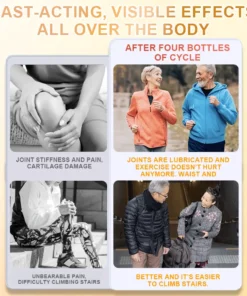

Melittin‘s anti-inflammatory action reduces the inflammatory response in arthritis, thereby diminishing joint pain and swelling, and enhancing joint flexibility. Beyond its anti-inflammatory and pain-relieving effects, Bee Venom also offers antibacterial, antitumor, cardiovascular protective, beauty, and anti-aging benefits.

When applied topically, Bee Venom interacts with pain perception receptors and inflammatory pathways in the skin. This interaction can modulate inflammatory processes, potentially reducing the release of pro-inflammatory molecules that contribute to joint and bone swelling.